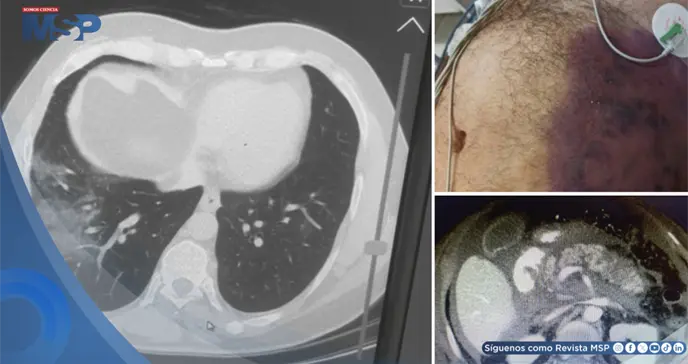

Para confirmar el diagnóstico y evaluar la extensión del daño, se realizó una tomografía computarizada abdominal con protocolo pancreático.

Las imágenes revelaron una pancreatitis necrosante aguda severa, con más del 30% del tejido pancreático afectado por necrosis y acumulación de líquido inflamatorio en los espacios circundantes.

La tomografía computarizada es fundamental no solo para el diagnóstico, sino también para estadificar la enfermedad; las imágenes de este paciente mostraron el grado más severo, con múltiples colecciones de líquido.